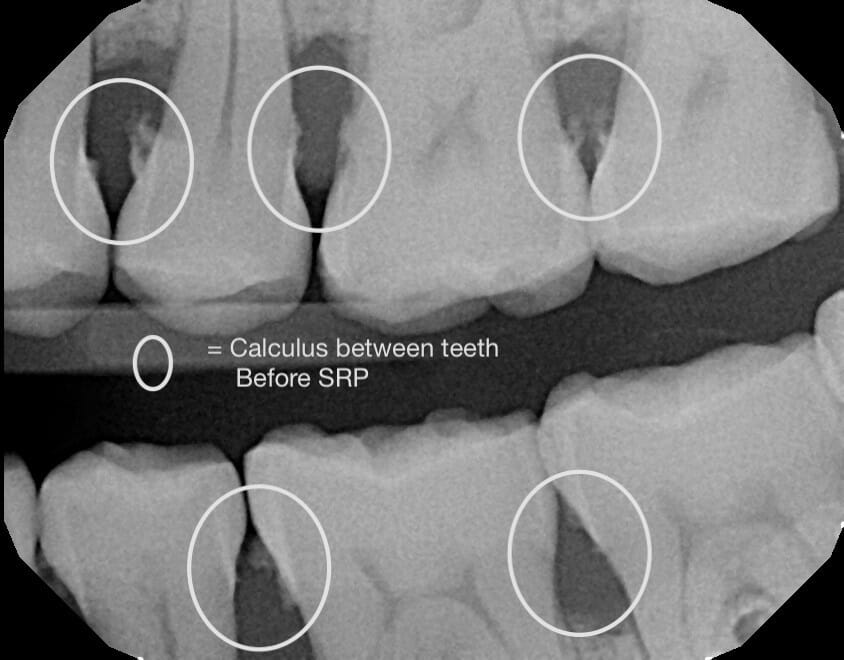

Scaling and Root Planing (SRP), which is commonly referred to as a deep cleaning or gum therapy, is the removal of plaque along with smoothing the roots of your teeth. And when patients who visit our office are diagnosed with gum disease, a deep cleaning is what we’ll recommend.

Some typical signs of gum disease that we most commonly see in the office are swollen and bleeding gums (especially while brushing), calculus near or below your gums, bad breath, and pain in your gums.

However, having one or many of these symptoms doesn’t mean that you can’t dramatically improve your oral health. Depending on the stage and severity of your condition, the deep cleaning you’ll receive at MFD – in combination with improved habits and oral hygiene that we’ll cover – can help you get back on the right path for your gums and teeth.